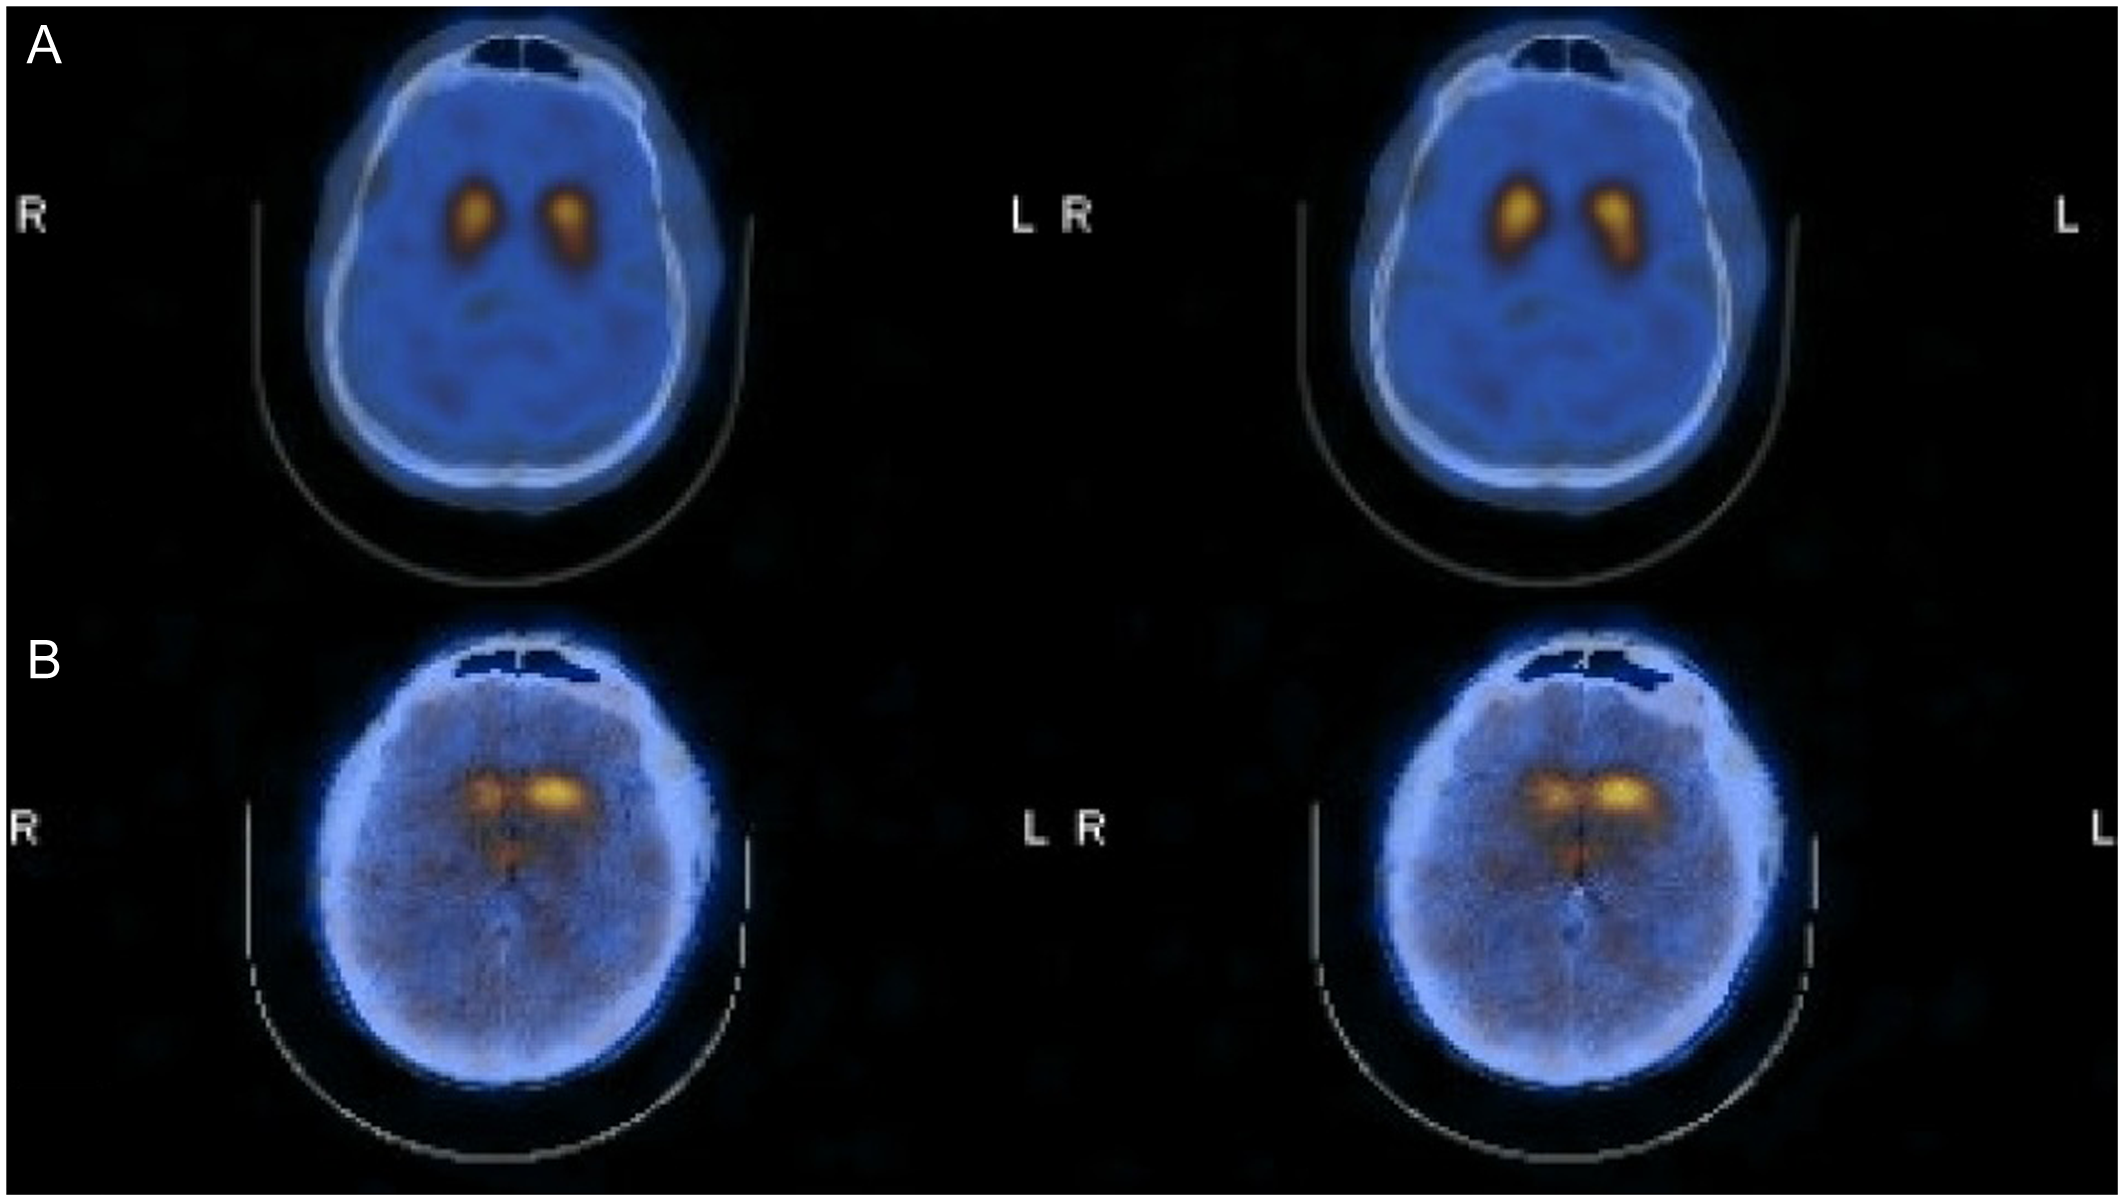

Overall, 27 of the 42 DaTscans (64%) were reported as “Abnormal,” and 15 (36%) were reported as “Normal.” Representative images of Normal and Abnormal DaTscans are shown in Figure 1. The distribution of these results by pre-DaT diagnosis is shown in Table 2. All 14 patients (100%) with a pre-DaT diagnosis of “PD” had an abnormal scan. In contrast, six of eight patients (75%) with “SP” had a normal scan. The “TS” group was mixed, with 11 patients (55%) having an abnormal scan and 9 (45%) having a normal scan.

Figure 1. Representative DaTscan images. Top row (Normal): Displays symmetrical, intense radiotracer uptake in the striatum with a characteristic “comma” shape, indicating preserved presynaptic dopamine transporters in both the caudate and putamen. This pattern supports a non-neurodegenerative diagnosis (e.g., essential tremor). Bottom row (Abnormal): Displays reduced uptake, particularly in the putamen (posterior striatum), resulting in a “period” or circular appearance. This loss of the “comma” tail indicates a presynaptic dopaminergic deficit consistent with neurodegenerative parkinsonism (e.g., Parkinson’s disease). Note: DaT = dopamine transporter.